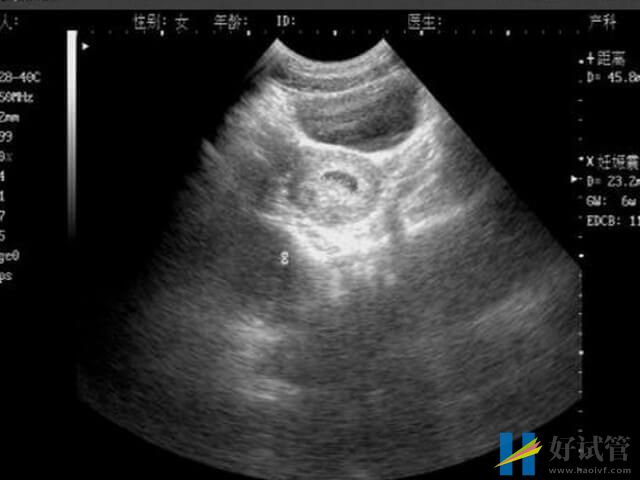

胎停在临床中称为胚胎停育,是指由于某种原因导致的胚胎停止发育,可进一步引起胚胎死亡。一般来说,胎停的发生概率最好的阶段就是怀孕早期的时候,其原因大致就如下所列:

当胚胎质量存在问题,如存在染色体异常等情况的时候,就容易导致怀孕早期的胚胎发育不完善的情况,此时有没有胎盘的保护,所以极易容易出现胎停的情况。

当胚胎着床不稳定的时候,随着怀孕天数的增加,体内分泌的hcg等激素也无法达到孕育胚胎生长所需,而得不到充足营养物质的胚胎,就有可能会发生胎停育的情况。

3、胎盘没形成

胎盘是能够给胚胎运输营养物质的,能帮助胎儿抵御外界的病毒、真菌、细菌等病原体,从而降低发病率等,而在怀孕早期的时候,胎盘没有形成,胎儿就有可能因无法摄取足够营养、被病原体感染等,而导致胎停育的现象。